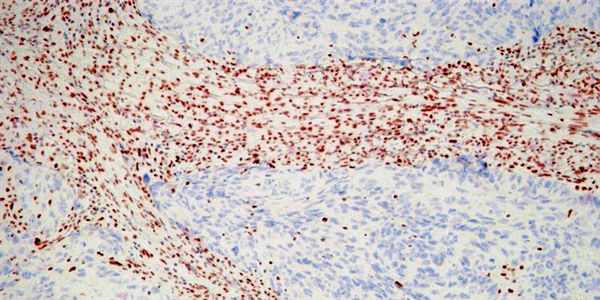

Чтобы безошибочно установить гистологический тип опухоли в затруднительных ситуациях, вызванных, к примеру, маленьким размером образца или утратой опухолевыми клетками способности к образованию специфических структур (низкая степень дифференцировки), или выявить некоторые специфические характеристики новообразования, морфологи используют иммуногистохимическое окрашивание (ИГХ). Этот метод сформировался еще в середине 1980-х годов [2] и сразу стал одним из наиболее востребованных в клинической онкологии (рис. 3). Появление такого диагностического теста, например, существенно изменило роль патоморфологического исследования в лечении рака молочной железы: именно от результатов ИГХ-анализа на рецепторы к эстрогенам (ER) и прогестерону (PgR), которые синтезируется опухолевыми клетками при этом заболевании, зависит назначение эндокринной терапии. В настоящее время антагонисты эстрогенов, замедляющих деление клеток рака молочной железы, принимают примерно 70% пациенток [3]. С помощью ИГХ можно также обнаружить увеличение синтеза онкобелка HER2/neu (от англ. human epidermal growth factor receptor — рецептор эпидермального фактора роста, или трансмембранная рецепторная тирозинкиназа). Опухоли, вырабатывающие HER2/neu, оказались чувствительными к терапевтическим ингибиторам этой тирозинкиназы, и назначение соответствующих лекарственных препаратов (например, трастузумаба) основано на результатах тестов, в числе которых и ИГХ-анализ [4].

Рис. 3. Схема иммуногистохимического (ИГХ) метода и примеры его применения. Первичные антитела связываются с искомым антигеном (гормоном или его рецептором) и становятся видны в световой микроскоп благодаря соединению с вторичными антителами, мечеными ферментом, при этом пероксидазная активность выявляется с помощью 3,3-диаминобензидина (DAB). Справа приведены примеры оценки рецепторного статуса карцином молочной железы: ИГХ-реакция с антителами к рецепторам эстрогенов (а — негативная реакция, б — ядерное окрашивание, 100% клеток) и с антителами к HER2/neu (в — мембранное окрашивание, оценка 3+)

Диагностику опухолей сегодня невозможно представить без сочетания традиционного морфологического и молекулярно-генетического анализа. Первые мутации, ассоциированные с ответом опухолей на терапию, были обнаружены в прошлом десятилетии. Уже сейчас онкологические клиники применяют десятки молекулярных тестов, предназначенных для персонализации лечения. Еще недавно клиническое деление всех первичных опухолей легкого на мелкоклеточный и немелкоклеточный рак было достаточным для определения стратегии лечения. Ситуация изменилась с открытием активирующих мутаций в гене, который кодирует рецептор эпидермального фактора роста — EGFR, сделавших этот онкогенный белок избирательной мишенью для воздействия препаратов ингибиторов EGFR. Мутации EGFR, как правило, встречается у пациентов с аденокарциномой легкого. Таким образом, актуальной задачей стала дифференциальная диагностика между аденокарциномой и другими гистологическими разновидностями. Маркером первичных аденокарцином является ядерный белок TTF-1 [5]. Если ядра раковых клеток демонстрируют положительное окрашивание (рис. 4), то патоморфолог ставит диагноз «аденокарцинома», и в этом случае пациенту целесообразно подвергнуться молекулярному тестированию на предмет наличия в опухоли мутаций EGFR.

Рис. 4. Низкодифференцированная аденокарцинома легкого (а, среди фиброзной ткани отдельно расположенные опухолевые клетки) и положительная ИГХ-реакция с антителом к TTF-1 в ядрах опухолевых клеток (б)